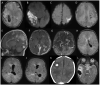

Figures